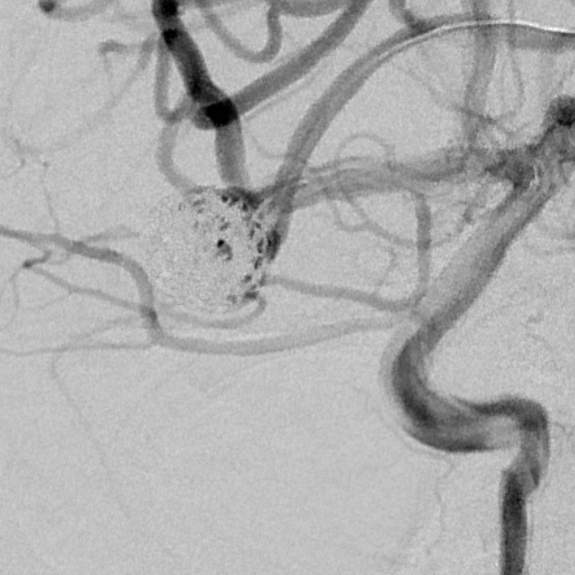

粗大分支从破裂瘤体上发出来,急性期能单纯致密栓塞吗?

病史:中年女性,新冠感染,颅内动脉瘤破裂,Hunt-Hess 4级

最终,动脉瘤瘤体致密栓塞,各个分支保留良好